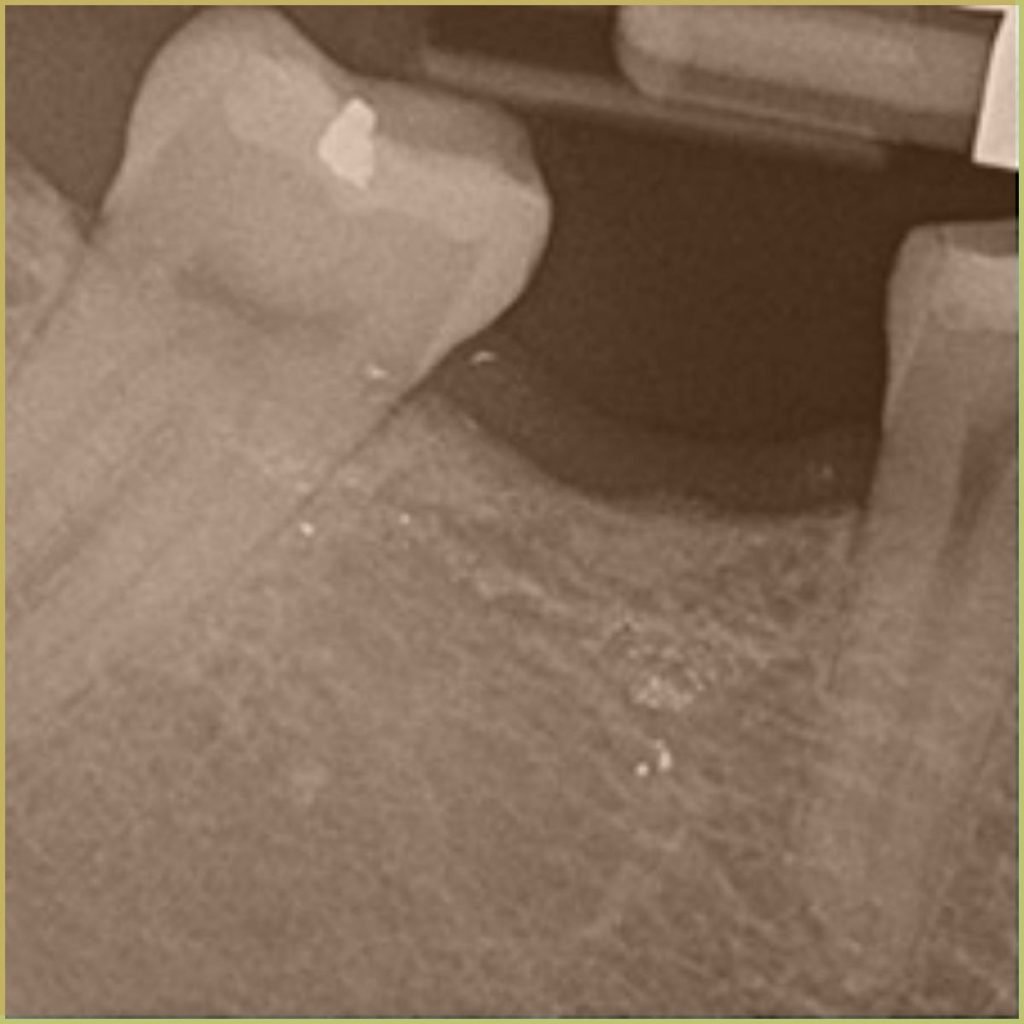

AMALGAM TATTOO

Amalgam Tattoo refers to the discoloration seen in oral tissues where dental amalgam has been deposited. The common clinical presentation includes:

- Well differentiated gray, blue or black focal macule.

- Asymptomatic lesions with no indication of associated inflammation.

- May be visible radiographically.

Diagnosis is based on the lesion history, clinical presentation, and radiographic analysis only. If biopsied, microscopic findings may include:

- Fragments of metal within connective tissue.

- Metal staining of reticulin fibers.

- Particles may be surrounded by fibrous tissue.

- Granulomatous inflammation with a mixture of lymphocytes and plasma cells.

Your differential diagnosis should include:

- Melanoma.

- Vascular malformation.

- Nevus.

- Mucosal melanotic macule.

- Melanoacanthoma.

No treatment is required.